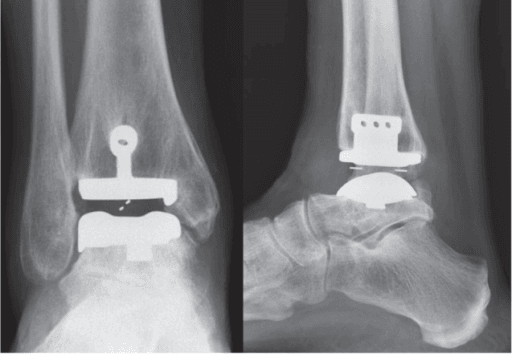

| Post-fixation assessment | Quantifies residual diastasis or rotational malreduction | Check reduction quality |

| Equivocal radiographs | Provides bilateral cross-sectional comparison | Resolve borderline cases |

Loaded Alignment Compared with Alternative Weight-Bearing Assessment

- WBCT provided weight-bearing alignment information while preserving superior osseous detail compared with lower-detail alignment studies.

- Cross-sectional reformats improved understanding of hindfoot and ankle position in complex deformity.

- The study supported WBCT as a combined alignment-and-planning test for selected cases.